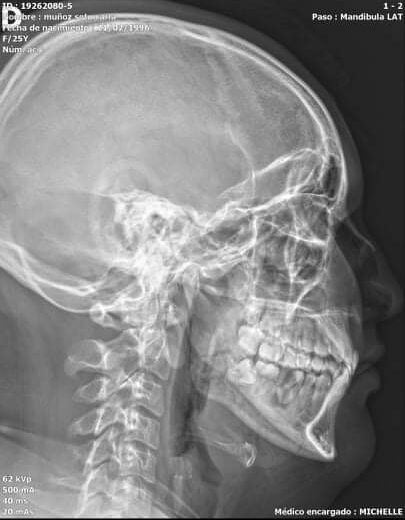

(Santiago de Chile, 30 de noviembre de 2021).- Carlos, chique trans masculino fue agredide junto a su pareja por seis personas en la empresa Garcés Fruit, ubicada en San Francisco de Mostazal. Ambes sufrieron golpes en sus rostros y cuerpos, quedando Carlos con una herida en la ceja y fracturas en su mandíbula, en la actualidad se encuentra hospitalizade y su pareja con una lesión en la rodilla.

Carlos relata a la abogada Emilia Oyarzún, pasante de la Unidad de Legislación y Políticas Públicas OTD Chile, que en dos semanas de trabajo en Garcés Fruit no respetaron su identidad de género, además de recibir insultos, hostigamiento y descalificaciones por parte de sus compañeres, quienes concretaron sus amenazas golpéandole junto a su pareja el jueves 25 de noviembre en horas de la tarde. La empresa no ha reconocido dicho ataque transodiante y se ha negado a cubrir los gastos médicos.